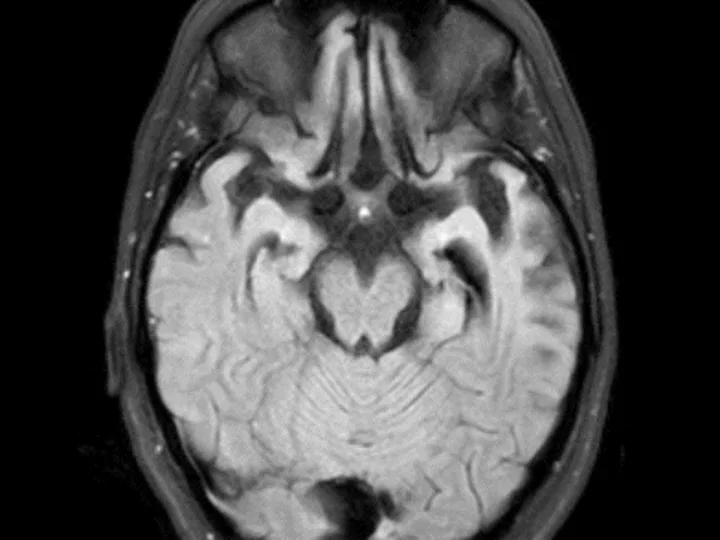

Dr. Vossel’s clinical studies with Alzheimer’s disease (AD) patients revealed that over 40% of patients exhibit silent epileptiform activity, mostly occuring during sleep, and this subclinical phenomenon can accelerate disease progression. Additionally, an estimated 20% of Alzheimer's patients develop seizures and associated cognitive decline. Therefore, up to 60% of Alzheimer's patients have seizures or epileptiform activity and could benefit from anti-seizure treatments. In a Phase 2a study, we showed that low doses of the anti-seizure drug levetiracetam improves spatial memory and executive function in patients with AD and detectable epileptiform activity. The Vossel lab has also demonstrated that patients with dementia with Lewy bodies have increased risk of seizures and myoclonus, which can hasten cognitive decline. To further understand seizure/epileptiform activity’s contribution to network dysfunction in dementia, the Vossel Lab uses electroencephalography (EEG) recordings in mice treated with antiseizure drugs or tau modifications. Studies using EEG recordings in models of neurodegenerative disease provide valuable insight into assessing how the blockade of certain biological processes may ameliorate overall network dysfunction.